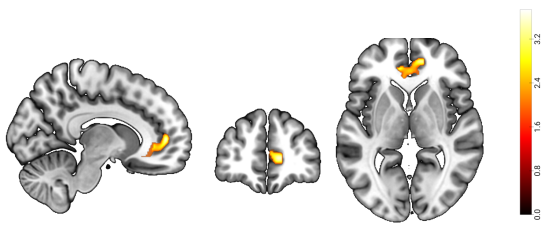

近日,西南大学365上市公司(英国)集团冯廷勇教授团队在国际著名学术期刊《Behavioral and Brain Functions》(中科院分区SCI一区,IF = 5.1)上发表了名为“The vmPFC-IPL functional connectivity as the neural basis of future self-continuity impacted procrastination: the mediating role of anticipated positive outcomes”的学术论文。该研究基于预期想象的2(指向性:任务过程VS.任务结果)×2(情绪效价:正性VS.负性)模型(Yang & Feng, 2021),采用自由建构范式,收集被试的预期想象想法,并结合基于体素的形态学分析(VBM)和静息态功能连接(RSFC)两种多模态分析方法,深入探究了未来自我连续性影响拖延的神经基础。该研究发现:(1)行为结果表明,未来自我连续性与拖延行为呈负相关关系(见图1);(2)VBM结果发现,未来自我连续性与右侧腹内侧前额叶(right ventromedial prefrontal cortex,RvmPFC)的灰质体积呈正相关关系(见图2);(3)RSFC分析揭示,右侧腹内侧前额叶与左侧顶下小叶(left inferior parietal lobule, LIPL)之间的功能连接(RvmPFC-LIPL)强度与未来自我连续性呈正相关关系(见图3);(4)中介分析发现,预期想象正性结果在未来自我连续性的功能连接(RvmPFC-LIPL)对拖延行为的影响中起到了完全中介的作用(见图4)。基于拖延的时间决策模型(Zhang & Feng, 2020),这些结果说明,未来连续性主要通过预期想象增加正性结果价值,进而减少了拖延行为。本研究从认知神经角度系统地解答了“未来自我连续性通过什么心理过程减少拖延行为”,也为拖延的干预提供了新的视角和理论依据。

图3 右侧腹内侧前额叶与左侧顶下小叶的功能连接与未来自我连续性呈显著正相关